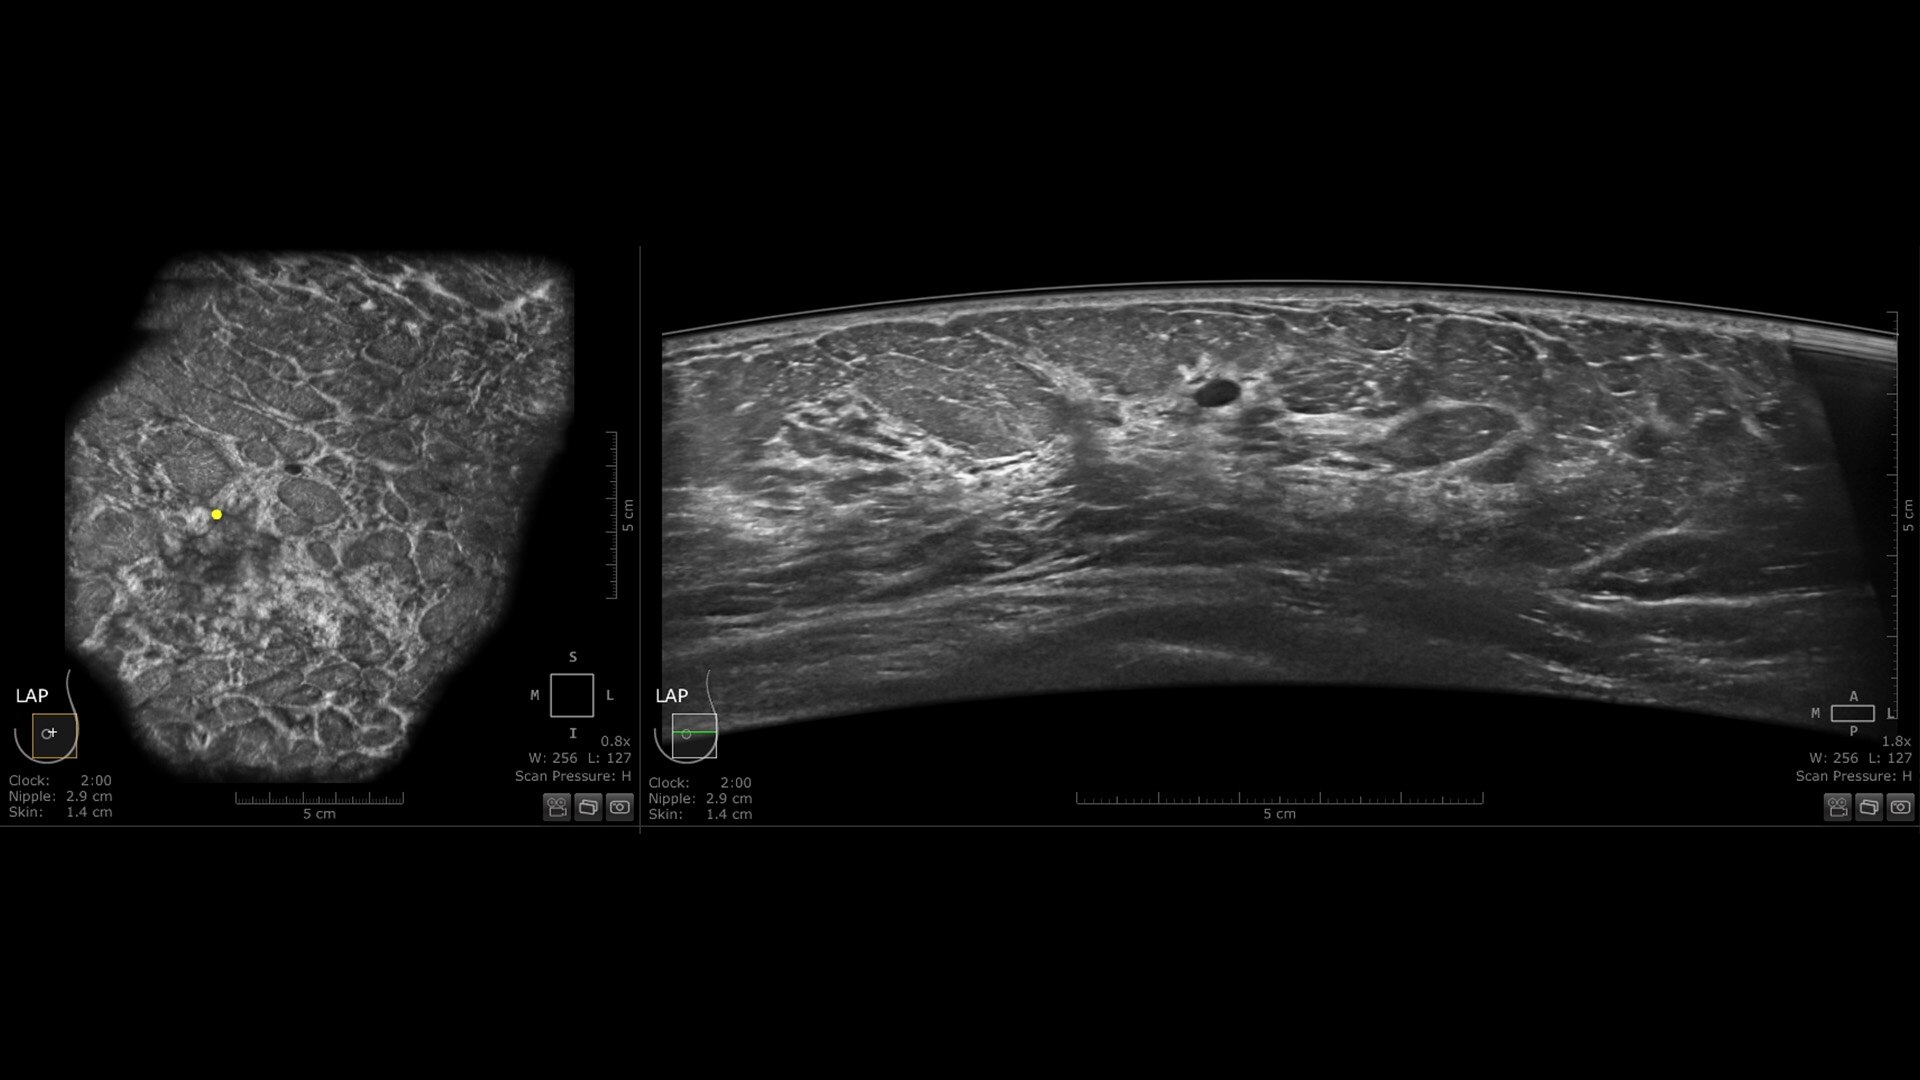

Invenia ABUS Premium: an innovative AI-driven 3D ultrasound solution for patients with dense breasts

Invenia ABUS is the first FDA-approved supplemental ultrasound screening technology that is specifically designed for detecting cancer in dense breast tissue. Embrace the new era of breast ultrasound with our comprehensive, non-invasive, patient-friendly solution for screening and beyond.

The latest innovation in breast ultrasound

The Invenia ABUS Premium is designed for high patient throughput and extraordinary image quality to provide a great level of confidence. With its innovative design, it’s easy to use, reproducible, user-independent, standardized and allows reading anywhere.

The novel Reverse Curve™ transducer is designed for enhanced performance

Its gentle 15.3 cm shape follows the breast's natural contour, enhancing patient comfort* and ensuring full contact for comprehensive coverage. The improved image quality* increases diagnostic confidence for reading ABUS exams.

Excellent image quality and 40% faster scan speed

• cSound Imageformer, software-based processing, produces exquisite, reproducible images by leveraging automatic focus at every pixel.

• Fast Scan increases scan speed by 40%*, fostering improved efficiency and patient throughput.